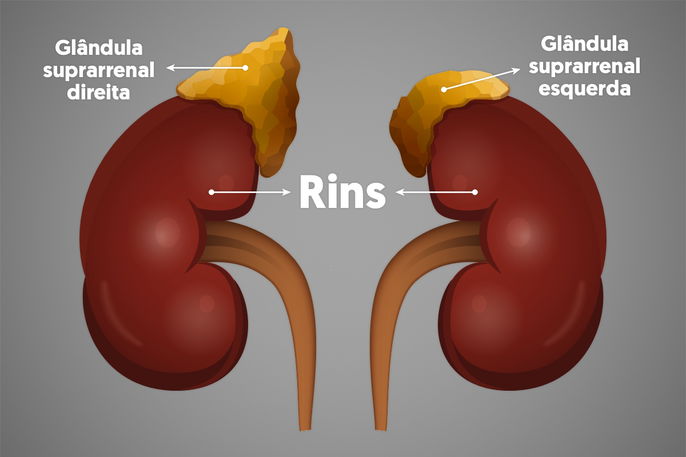

A Doença de Addison, também conhecida como insuficiência adrenal primária, é uma condição que afeta as glândulas suprarrenais, responsáveis pela produção de hormônios vitais como o cortisol e a aldosterona. Quando essas glândulas não funcionam adequadamente, o corpo sofre com a baixa produção desses hormônios, impactando diversas funções essenciais, desde o metabolismo até a resposta ao estresse. A alimentação, nesse contexto, assume um papel de protagonista na gestão da doença, atuando como um pilar fundamental para a qualidade de vida do paciente.

Para quem vive com a Doença de Addison, o sódio deixa de ser um vilão e passa a ser um aliado importante. A baixa produção de aldosterona leva a uma excreção aumentada de sódio pelos rins, o que pode resultar em desequilíbrios eletrolíticos perigosos. Por isso, a recomendação é, na maioria dos casos, um aumento na ingestão de sal (sódio) na dieta.

Em contrapartida ao sódio, o potássio exige atenção e controle na dieta para a Doença de Addison. Embora seja um mineral essencial para diversas funções corporais, seu excesso pode ser prejudicial, especialmente quando a função adrenal está comprometida. O desequilíbrio entre sódio e potássio pode agravar os sintomas da condição.